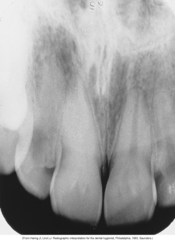

interproximal moderate caries

Front

Back